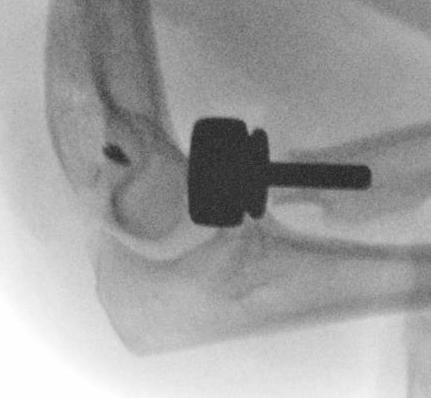

Overstuffing

| Lesser sigmoid notch | Symmetry of ulnohumeral joint |

|---|---|

|

Radial head shoulder articulate with lesser notch

Ensure no gapping of lateral ulnohumeral joint |

- cadaveric study

- increased medial ulno-humeral joint line gapping with overlengthening of 6 or 8 mm

- increased lateral ulno-humeral joint line gapping with overlengthening of 2 mm